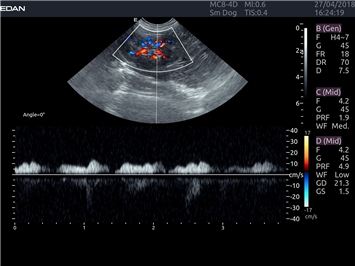

Цветовой допплер:

Да

Импульсно-волновой допплер:

Триплексное сканирование:

Дуплексное сканирование: